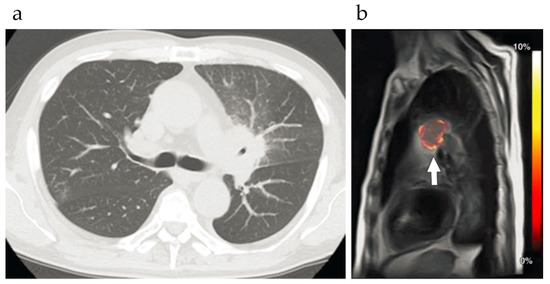

- Jones, K.; Stuehm, C.; Hsu, C.; Kuo, P.; Pagel, M.; Randtke, E. Imaging Lung Cancer by Using Chemical Exchange Saturation Transfer MRI With Retrospective Respiration Gating. Tomography 2017, 3, 201–210. [Google Scholar] [CrossRef]

- Ohno, Y.; Kishida, Y.; Seki, S.; Yui, M.; Miyazaki, M.; Koyama, H.; Yoshikawa, T. Amide proton transfer-weighted imaging to differentiate malignant from benign pulmonary lesions: Comparison with diffusion-weighted imaging and FDG-PET/CT. J. Magn. Reson. Imaging 2018, 47, 1013–1021. [Google Scholar] [CrossRef] [PubMed]

- Ohno, Y.; Yui, M.; Koyama, H.; Yoshikawa, T.; Seki, S.; Ueno, Y.; Miyazaki, M.; Ouyang, C.; Sugimura, K. Chemical Exchange Saturation Transfer MR Imaging: Preliminary Results for Differentiation of Malignant and Benign Thoracic Lesions. Radiology 2016, 279, 578–589. [Google Scholar] [CrossRef] [PubMed]